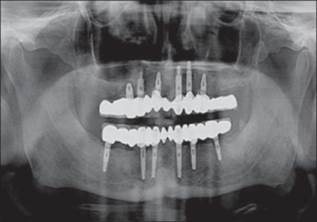

Un paciente de sexo masculino de 58 años había acudido al ala de pacientes externos de nuestro departamento, con una queja principal de falta de diente en los arcos maxilar y mandibular. El paciente quiere tener una prótesis fija ya que no estaba contento con la dentadura convencional [Figura 1] y [Figura 2] . Se registró un historial de casos adecuado para el paciente, incluido un historial médico que no era contributivo, con pruebas de laboratorio relevantes, exámenes dentales y orales. Se prepararon impresiones de diagnóstico y moldes. Se realizó un examen exhaustivo y el paciente estaba motivado para implantar prótesis. El mapeo óseo se realizó para evaluar el ancho del hueso, mediante el uso de ortopantamografía (OPG), se calculó la longitud del hueso disponible y se seleccionaron los implantes de tamaño apropiado [Figura 3]. Se preparó una plantilla quirúrgica para el maxilar y la mandíbula, y la posición de los implantes se decidió antes de la cirugía colocando un taladro en el implante.

Figura 3: Mapeo óseo y radiografía preoperatoria |

Se planificó un protocolo quirúrgico de dos etapas y se le pidió al paciente que tomara antibióticos y analgésicos antes de la cirugía. El colgajo mucoperióstico se elevó por todo el maxilar superior y la plantilla se colocó en la cresta de la cresta con broca piloto se lleva a cabo [Figura 4] y [Figura 5] . Se colocan herramientas paralelas y se verifican las angulaciones del implante. Se utilizaron taladros secuenciales y se colocaron implantes en el sitio de osteotomía y se introdujeron en el sitio hasta que se enterraron todos los hilos. Se colocaron tornillos de cubierta y se realizó la sutura [Figura 6]. La atención postoperatoria se ha administrado con antibióticos, analgésicos y enjuagues bucales. Se sugirió mantener la higiene bucal y la compresa de hielo si fuera necesario. Se siguió un procedimiento similar para la mandíbula y se realizó la sutura [Figura 7] . Después de 3 meses, el paciente fue retirado del mercado y se realizó una OPG postoperatoria y se verificó su adecuada osteointegración. Después de confirmar la osteointegración, el colgajo se elevó y se retiraron los tornillos de cobertura y se colocó por extensión de la mucosa y esperó durante una semana para que se produzca la curación (Adell R, etal., 1981) [Figura 8] .

El tratamiento del edentulismo parcial y total con implantes dentales se ha convertido en un procedimiento predecible para la mayoría de los pacientes y se espera que desempeñe un papel importante en la rehabilitación oral. La colocación quirúrgica de implantes dentales es un tratamiento bien documentado para el edentulismo (Adell et al., 1990). Las tasas de éxito del tratamiento son altas y las complicaciones postoperatorias fueron relativamente modestas. El tratamiento exitoso de implantes implica la osteointegración de implantes que se colocan en posiciones ideales para la fabricación de una prótesis dental (Jacobs et al., 1999). La evaluación clínica periódica del accesorio del implante, la prótesis y el tejido circundante es crítica para el éxito clínico. En el presente caso, el paciente fue llamado por cada 3, 6 y 12 meses, se realizó la extracción profesional de depósitos supragingivales y subgingivales de forma regular [Figura 10] .

Figura 10: Radiografía postoperatoria de seis meses